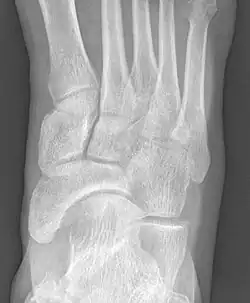

Radiological images

-

From left to right: Type 1, 2 and 3 -